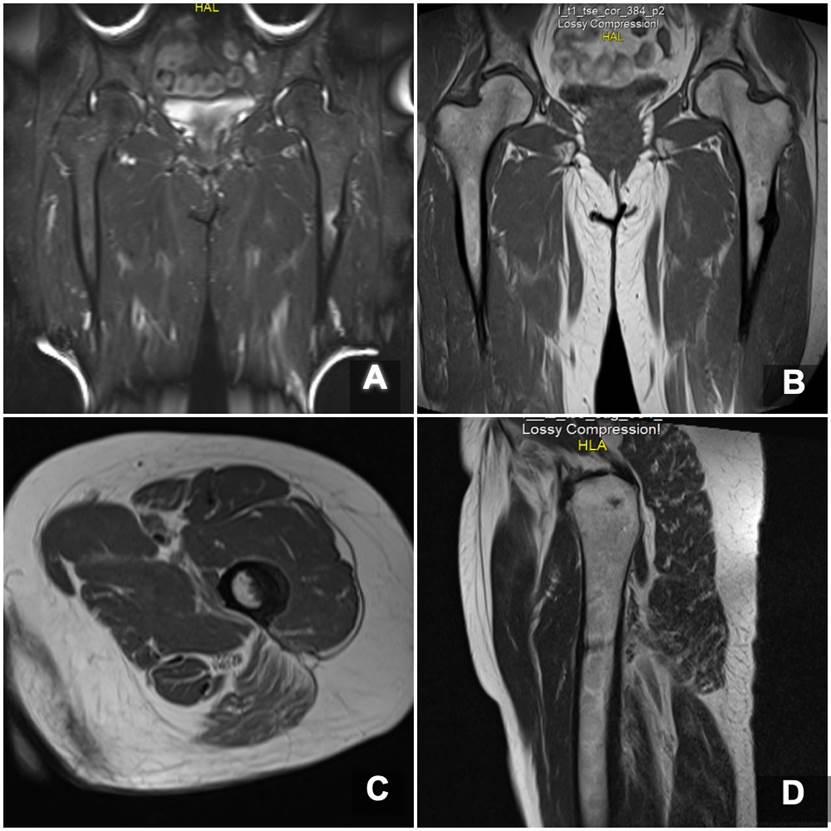

Ante estos hallazgos de imágenes, la paciente suspendió el uso de alendronato. En las imágenes de resonancia se confirma un trazo de fractura transverso no desplazado a nivel de la región subtrocantérica de fémur izquierdo en la zona del dolor (Figura 3).

Imagen de resonancia magnética en cortes coronales con secuencia STIR (A) y secuencia T2 (B), e imágenes en cortes axiales en secuencia T2 (C) y sagitales (D), donde se evidencia un engrosamiento del periostio en la cortical lateral de la región subtrocantérica de fémur izquierdo, a partir de la cual se origina un trazo de fractura incompleto en sentido transverso hacia la cortical medial.

Figura 3: Imagen de resonancia magnética en cortes coronales con secuencia STIR (A) y secuencia T2 (B), e imágenes en cortes axiales en secuencia T2 (C) y sagitales (D), donde se evidencia un engrosamiento del periostio en la cortical lateral de la región subtrocantérica de fémur izquierdo, a partir de la cual se origina un trazo de fractura incompleto en sentido transverso hacia la cortical medial.

En general, las FAF se presentan como un trazo transverso generalmente, sin conminución, con un engrosamiento endóstico de la cortical lateral. Existen criterios menores asociados a las FAF, pero que no se requieren para del diagnóstico. En caso de presencia de síntomas prodrómicos (dolor en el muslo al apoyar la extremidad) suele indicarse estudio con resonancia magnética, en el cual se identifican con mayor precisión hallazgos como edema óseo, trazos de fracturas ocultas o puede ser más evidente el engrosamiento endóstico (15). En caso de detectar estas fracturas ocultas o trazos incompletos, además de la suspensión del tratamiento con bifosfonatos, la suplementación de calcio y vitamina D, la restricción de carga de peso y limitación de actividad, la fijación profiláctica con clavo cefalomedular para la prevención de una FAF completa (16) ha demostrado resultar en mejores desenlaces y prevención de morbimortalidad de estos pacientes (17,18).